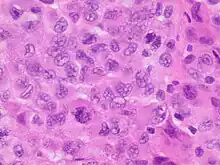

Adenosquamous carcinoma, with glandular features at left and squamous features at right. Anaplastic tumor cells.

Anaplastic tumor cells. Large cell carcinoma.